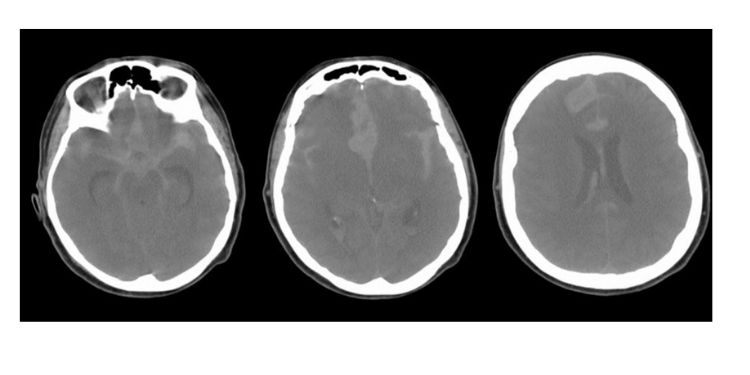

Exploring New Approaches in Brain and Spinal Cancer Treatment

Journal of Brain And Spinal Cancer focuses on the latest advancements in the diagnosis, treatment, and management of brain and spinal cancer. JBSC aims to provide a platform for researchers and clinicians to share their findings and contribute to the understanding and improvement of patient care.